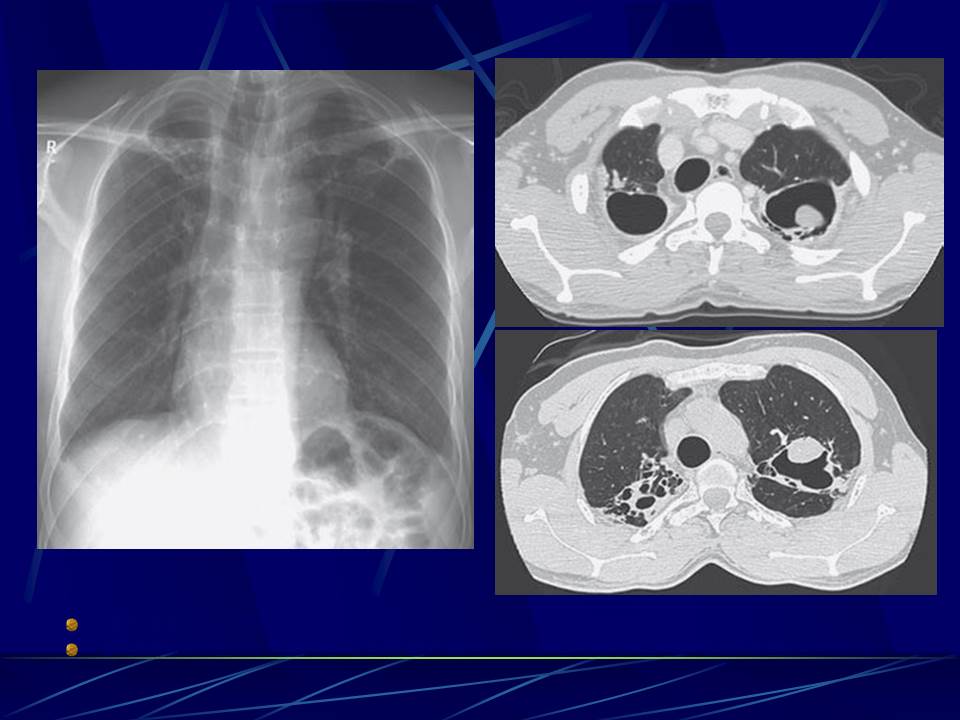

肺部真菌感染影像学分析